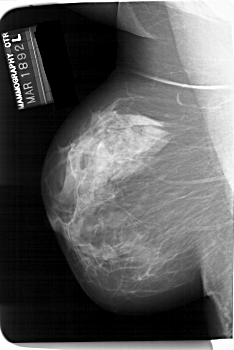

A_1414_1.LEFT_CC

LEFT_CC LINES 6811 PIXELS_PER_LINE 4126 BITS_PER_PIXEL 12 RESOLUTION 43.5 NON_OVERLAY